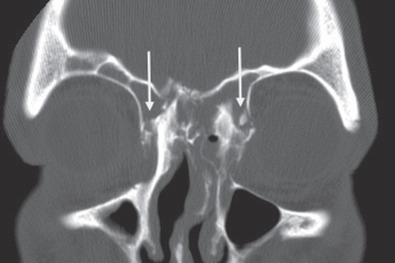

The gold standard radiographic examination for traumatic injuries of the facial skeleton is a thin cut (≤1 mm) computed tomography (CT) scan. To help improve diagnostic accuracy, these images should be reformatted into coronal, sagittal, and 3-dimensional reconstructions. The axial images are preferred for evaluation of the anterior and posterior table ( Fig. 1.7.4 ); sagittal images for the frontal sinus outflow tract and skull base ( Fig. 1.7.5 ); and the coronal images for the orbital roof/sinus floor ( Fig. 1.7.6 ). Three-dimensional reconstructions ( Fig. 1.7.7 ) offer a comprehensive view of the injury. They are helpful to assist in surgical planning, facilitate patient education, and delineate the size/location of bone fragments, which can reduce the need for soft tissue dissection.